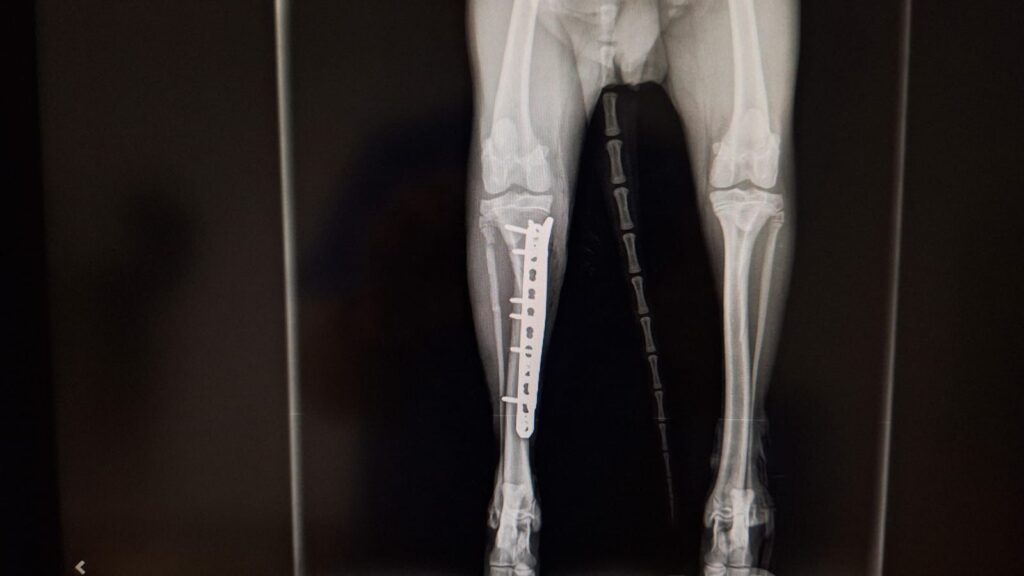

Kaiser braucht eure Hilfe

Kaiser wurde in Spanien überfahren und hat massive Verletzungen an 3 Beinen erlitten. Er wurde operiert und hat sich inzwischen auch schon recht gut erholt. Kaiser ist erst 9 Monate und ein sehr lieber und geduldiger Junge.